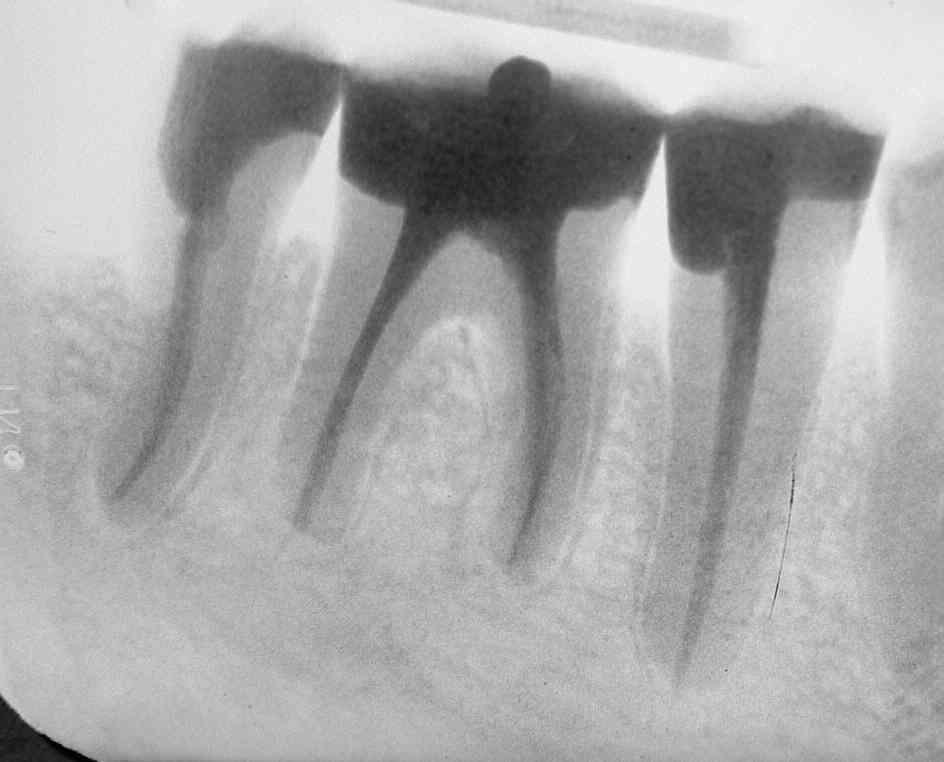

Unmittelbar nach WF im März 2001, mesiale Wurzel von 47 mit wegen geplanter Hemisektion mit provisorischer Wurzelfüllung mit Ca(OH)2 (Klick!)

Die Inversion des oberen Bildes verdeutlicht die massiven Aufhellungen an allen Wurzelspitzen und in der Furkation von 46  (Klick!)

Die Inversion des unteren Bildes beweist die völlige knochendichte Ausheilung an allen betroffenen Wurzeln. Sogar der von einigen Autoren geforderte durchgängige Peridontalspalt ist einwandfrei dargestellt  (Klick!).

Verlaufskontrolle mit praktisch vollständig knochendichtem  Umbau des Cerasorbs und weitgehend abgeschlossener Ausheilung aller apikalen Ostitiden im Februar 2002 (Klick!)